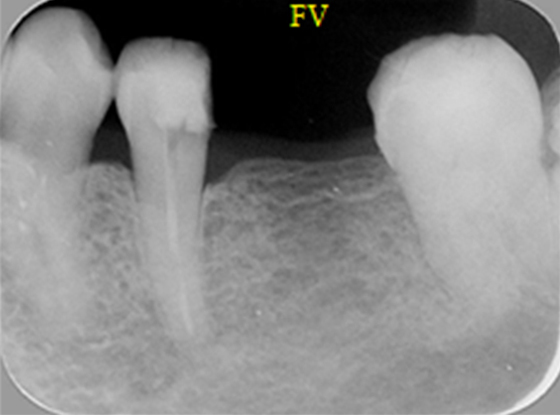

| 原因 | ブリッジ下の2次カリエス(虫歯の再発) 咬み合わせの不調和による咬合力の不均衡 |

| 治療法 | 矯正治療 自家歯牙移植 メタルボンドセラミッククラウン |

| 治療費(目安) | 自家歯牙移植 ¥54,000(料金改定前) メタルボンドセラミッククラウン 1歯¥10,8000(料金改定前) |